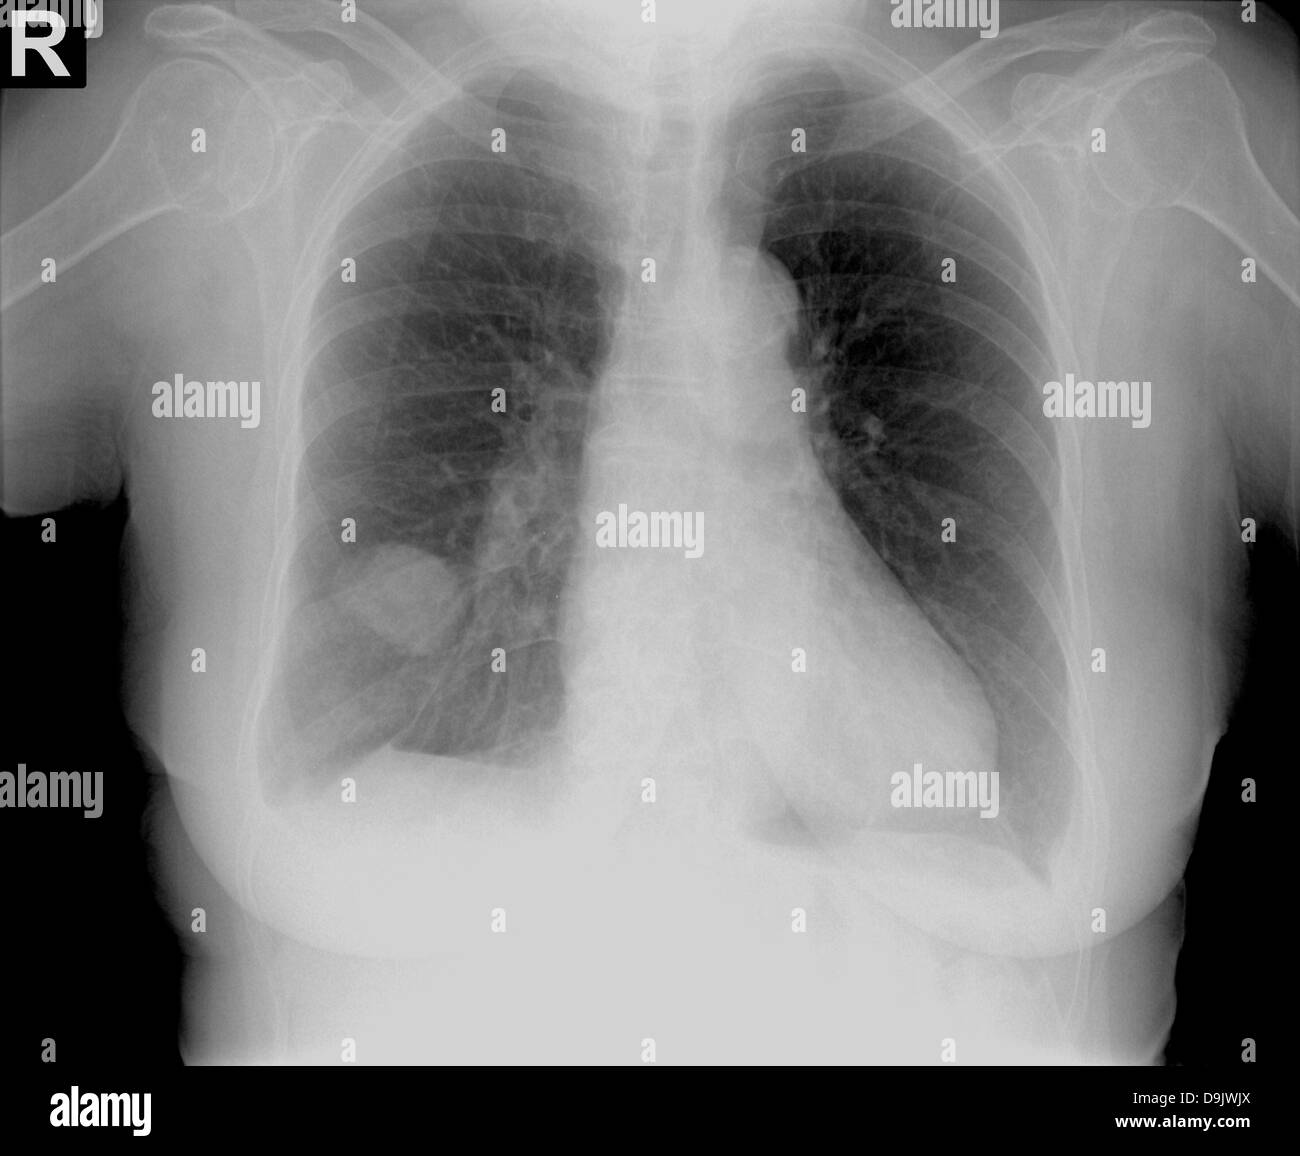

Chest xray with a round tumor on the right side Stock Photo Alamy Heart Tumor X Ray Multimodality imaging plays a pivotal role in diagnosis and surgical planning of cardiac masses. Cardiac myxoma is the most common primary cardiac tumor, usually found in the left atrium, and can cause various symptoms. In addition to radiologic evaluation of the mass itself, involvement of valvular apparatus, extent of. Metastases and pseudotumors (eg, thrombus) are much more common. Clinical features,. Heart Tumor X Ray.

Pancoast tumor chest x ray wikidoc Heart Tumor X Ray Primary cardiac tumors are very rare; Cardiac myxoma is the most common primary cardiac tumor, usually found in the left atrium, and can cause various symptoms. They can be either benign (noncancerous) or. Cardiac tumors (also called heart tumors) are growths that form in your heart. Multimodality imaging plays a pivotal role in diagnosis and surgical planning of cardiac masses.. Heart Tumor X Ray.